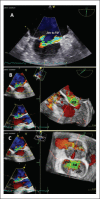

Three-dimensional Echocardiography Reveals the True Enemy in a Young Male with ST-Elevation Myocardial Infarction and Severe Mitral Regurgitation: Posterior Mitral Valve "Pseudo-Cleft" and Prolapse